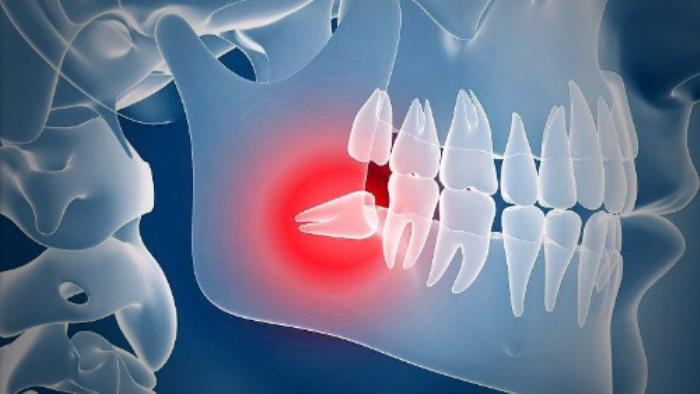

有网友提问智齿肿痛3天了,只能喝水、喝粥,医生,有没有什么好的办法?(网友是智齿冠周炎)

智齿疼痛感往往很强烈,使人食欲下降,晚上睡不好觉,严重影响个人生活和工作,情绪也会跟着变烦躁。

长歪的智齿常常会排挤前牙,甚至会顶坏前牙牙根。智齿不易清洁,牙周卫生不好的话,所以爆发龋齿、牙周病几率很高,还会连累前牙。

智齿问题也会影响到整个口腔健康,带来龋坏、前牙问题等,建议大家及早拔除。如果大家有类似情况的话,也尽量早点做检查,智齿问题一定要及早处理,以免后期出现更加严重的问题。